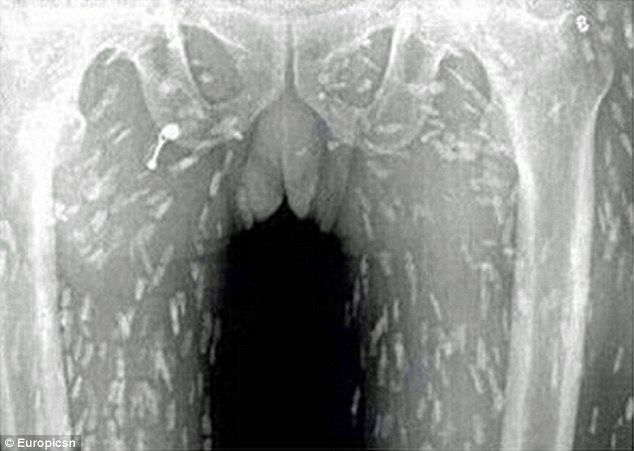

寿司好きの男性が体か痒い、胃が痛いと病院に行ったところ、全身から寄生虫が発見されるというショッキングな出来事がありました。中国のその男性は生魚のスライスを多く食べていたといいます。

感染すると数週間ほどで15mまで成長し、そして何年にもわたって生き続けます。場合によっては腸管以外の場所にも移動し、そこで卵を産み付けるのです。症状は疲労、便秘、腹部の不快感などと少なく、患者は比較的穏やかに過ごします。しかし最終的には肝臓、眼、心臓や脳などに寄生虫が移動し、その部位を食べることで生命を脅かす可能性があります。